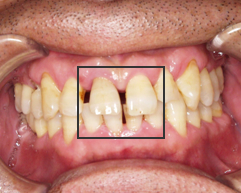

写真(1)

治療前歯がほとんどなくなっていて根っこだけの状態

歯周病の進行と舌圧の強さにより、下の前歯が前に飛び出てきてしまい上の前歯とぶつかるようになってきた。そのため咬む力によって歯が欠けてしまっている。

また、歯と歯の間に隙間が拡がってきている。

原因は、歯周病の進行と、舌圧による咬合不全。